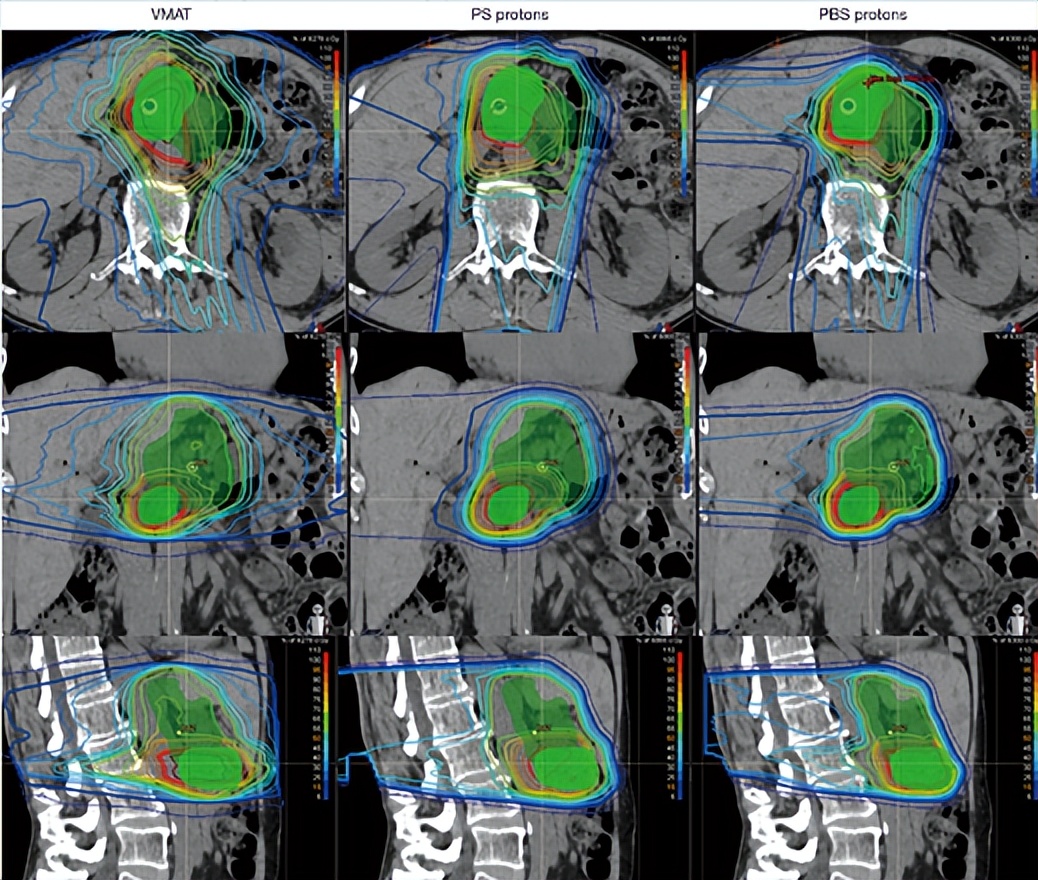

▲传统放疗、被动散射质子治疗和 (PS) 和笔形束扫描质子治疗 (PBS) 胰腺癌的剂量分布图,图源:参考来源[7]